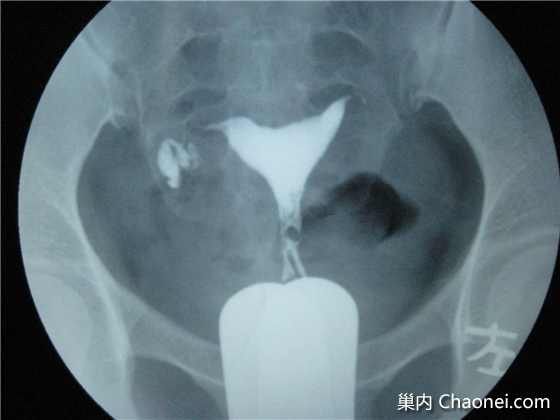

摘要:通草具有疏通输卵管堵塞的功效与作用。作为一种中药材,通草被广泛用于妇科领域,能够帮助疏通输卵管,提高受孕几率。其疗效受到许多女性的认可。通过服用通草,可以有效缓解输卵管堵塞带来的不适,促进血液流通,有助于恢复输卵管的正常功能。对于具体的疗效,还需根据个人体质和病情而定。

通草不仅可以帮助我们维持身体的正常功能,如促进血液循环、改善代谢等,更在女性健康方面发挥了重要作用,它能够减少体内炎症、改善血液流通,从而有助于输卵管的通畅,许多使用者的积极反馈都证明了通草在这一方面的显著效果。